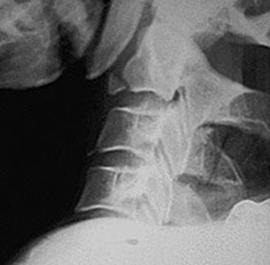

TRAUMA CERVICALA

Incidenta laterala Incidenta

laterala Incidenta

antero-posterioara

Fractura spanzuratului Fractura anterioara C4 Fractura C5 in lacrima in flexie

"in lacrima"

Fractura C5 "in lacrima" in extensie Luxatie fatetara

unilaterala Luxatie

fatetara bilaterala

C5 - C6 C5 - C6

Incidenta laterala Fractura Clay-Shoveler Luxatie atlanto-occipitala si